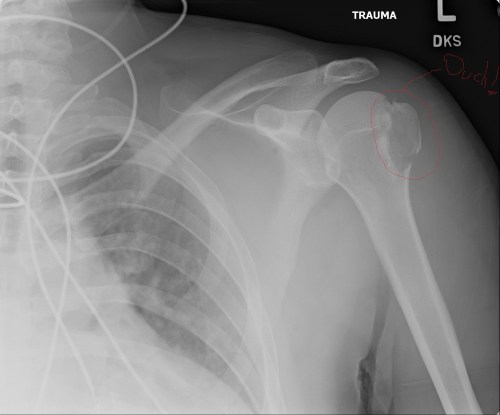

Left shoulder, with the offending greater tubercle/tuberosity of the humerus showing fracture(s).

Right shoulder x-ray, showing dislocation of the head of the humerus from the glenoid. Compare with above image- humerus has been shifted down. BUT no fractures, yay!

Right shoulder x-ray, showing dislocation of the head of the humerus from the glenoid. Compare with above image- humerus has been shifted down, the shoulder joint is facing you. BUT no fractures, yay!